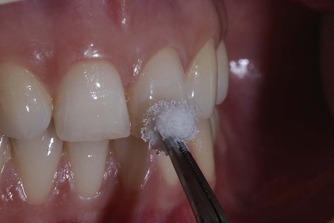

Pulp vitality test is crucial in monitoring the state of health of dental pulp, especially after traumatic injuries. The traditional pulp testing methods such as thermal and electric pulp testing methods depend on the innervation and often yield false positive and negative response. The newer pulp testing device, some of which are still under development stage, detect the blood supply of the pulp, through light absorption and reflection, are considered to be more accurate and non-invasive.